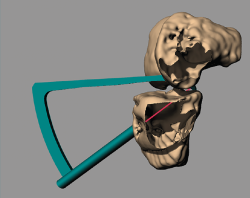

Figure 1. Design of the guide on the virtual reconstruction of the knee.

Using Rhinoceros®, Rhino 6 (TLM, Inc.), each guide was designed on a generic basis, followed by adaptation to the virtual reconstruction of the knee of each patient, with an entry point in the anteromedial cortical layer of the tibia located medial to the anterior tibial tuberosity (ATT), adapted to the bone relief, and two exit points in the insertion zone of the posterior horn of the internal meniscus (Figure 1). Each guide housed two 3-mm bores for the creation of two parallel tunnels (Figure 2). The tunnel angle was 60° in all cases, with variation in each case of the morphology of the intraarticular portion of the guide in order to fully adapt it to the anatomy and avoid impacting against the tibial spines or medial femoral condyle.

The virtual image of each knee was printed to create a 3D biological replicate of the joint using a Zortrax® M200 3D printer with high-impact polystyrene (HIPS) as material. Each guide was manufactured using polyamide (a heat-sterilisable material) and an HP® Jet Fusion 4210 printer (Figure 3). The biological replicates allowed virtual surgeries to check the guides for accuracy (Figure 4).

Figure 4. Printing of the biological replicate allows virtual surgery for assessing the position of the tunnels.